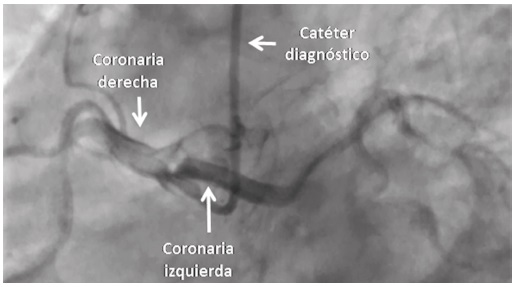

Durante la hospitalización en la unidad de dolor torácico, el paciente presentó nuevamente episodios recurrentes de angina, y a pesar de no tener cambios electrocardiográficos, se decidió hacerle coronariografía; en esta se hallaron las arterias coronarias epicárdicas sin lesiones ateroscleróticas significativas, pero con origen anómalo del tronco de la arteria coronaria izquierda, lo cual se observó en el aortograma; la imagen permitió localizar exactamente el sitio del ostium de la arteria y posteriormente canularla en forma selectiva; se determinó su ubicación precisamente en el seno coronariano derecho, contiguo al nacimiento de la arteria coronaria derecha (Figura 3).